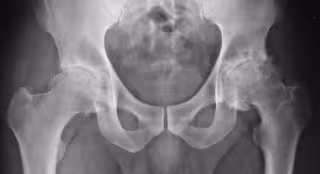

Investigadores de la Facultad de Medicina de la Universidad de Washington en St. Louis hn descubierto que la terapia génica probada en ratones ayudó a desarrollar fuerza y masa muscular significativa rápidamente, al tiempo que reducía la gravedad de la osteoartritis. También previno la obesidad, incluso cuando los ratones fueron alimentados con una dieta alta en grasas, según publican en la revista 'Science Advances'.

El ejercicio y la fisioterapia a menudo se recomiendan para ayudar a las personas que tienen artritis. Ambos pueden fortalecer los músculos, un beneficio que también puede reducir el dolor en las articulaciones, pero desarrollar masa muscular y fuerza puede llevar muchos meses y ser difícil frente al dolor en las articulaciones causado por la artrosis, particularmente para las personas mayores con sobrepeso.

La investigación muestra que la terapia génica ayudó a desarrollar una masa muscular significativa rápidamente y redujo la gravedad de la osteoartritis en los ratones, a pesar de que no hicieron más ejercicio. La terapia también evitó la obesidad, incluso cuando los ratones comieron una dieta extremadamente alta en grasas.

Los ratones también tenían menos daño de cartílago relacionado con la artrosis, un menor número de células y proteínas inflamatorias en sus articulaciones, menos problemas metabólicos y corazones y vasos sanguíneos más saludables que los compañeros de camada que no recibieron la terapia génica. También fueron significativamente menos sensibles al dolor.